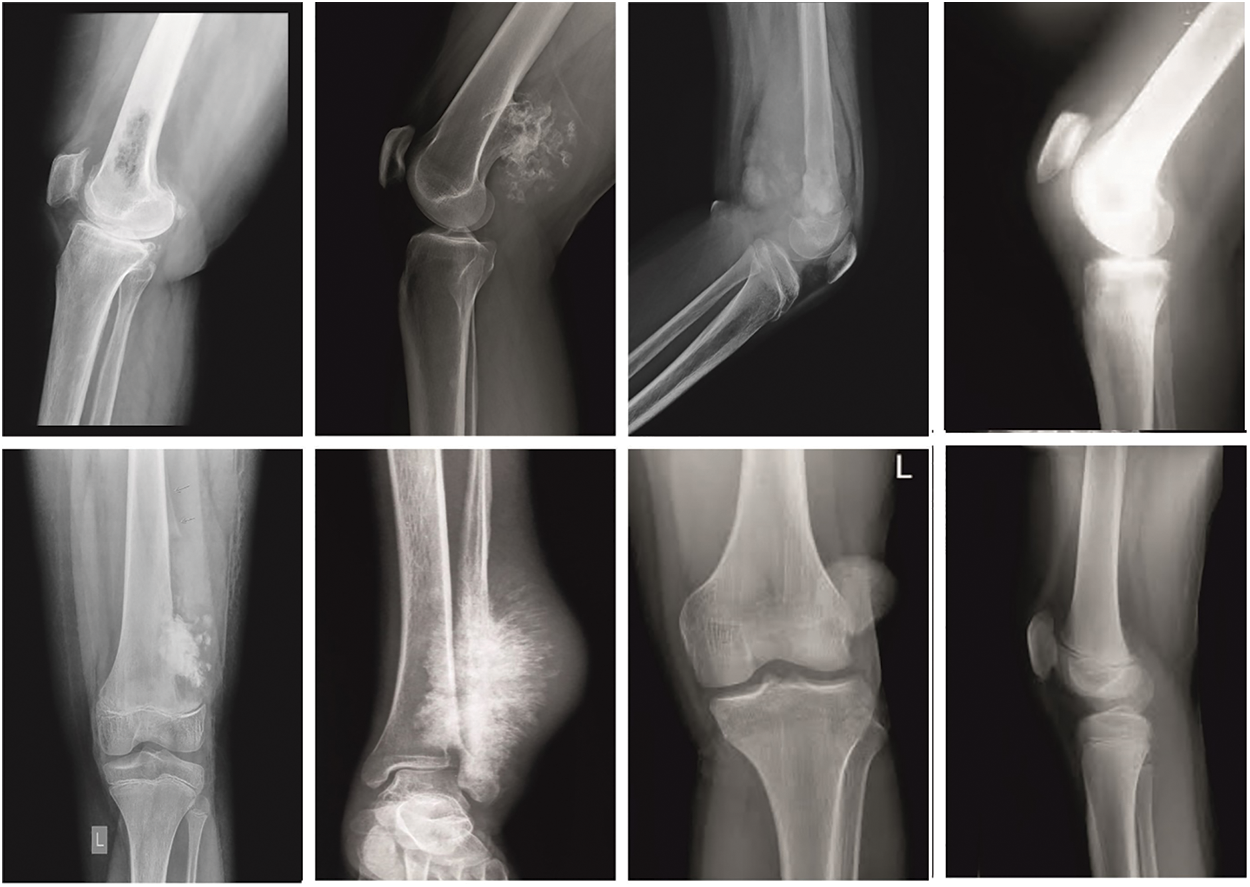

The proposed model is simulated using Python 3.6.5 tool on PC i5-8600k, GeForce 1050Ti 4 GB, 16 GB RAM, 250 GB SSD, and 1 TB HDD. The parameter settings are given as follows: learning rate: 0.01, dropout: 0.5, batch size: 5, epoch count: 50, and activation: ReLU. The performance of the ETSOTL-MIAS model on bone cancer classification performance is tested on a medical dataset comprising 100 samples with two classes as given in Table 1. Fig. 3 illustrates the sample images.

Figure 3: Sample images